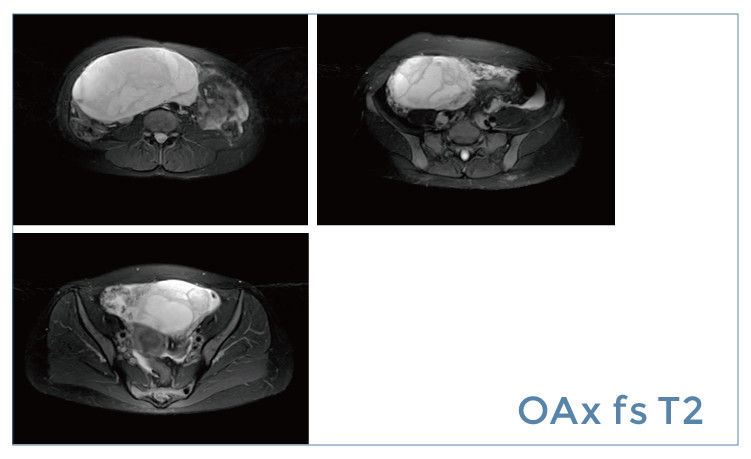

【朗润影像档案】20190412磁共振影像病例结果讨论

【朗润影像档案】磁共振影像病例分享(编号20190412)